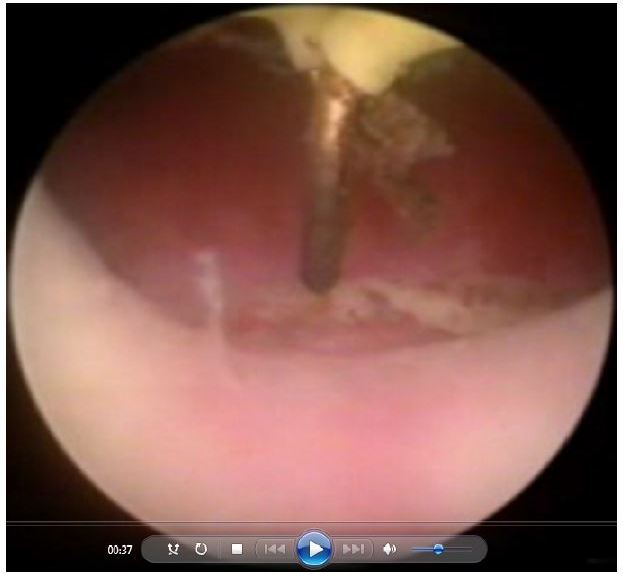

The fibroid pseudocapsule is composed of a rich neurovascular network in neurofibers similar to the neurovascular bundle surrounding the prostate.Continue Reading

The “cold loop” hysteroscopic myomectomy was presented at the beginning of the nineties for the first time at the NationalContinue Reading